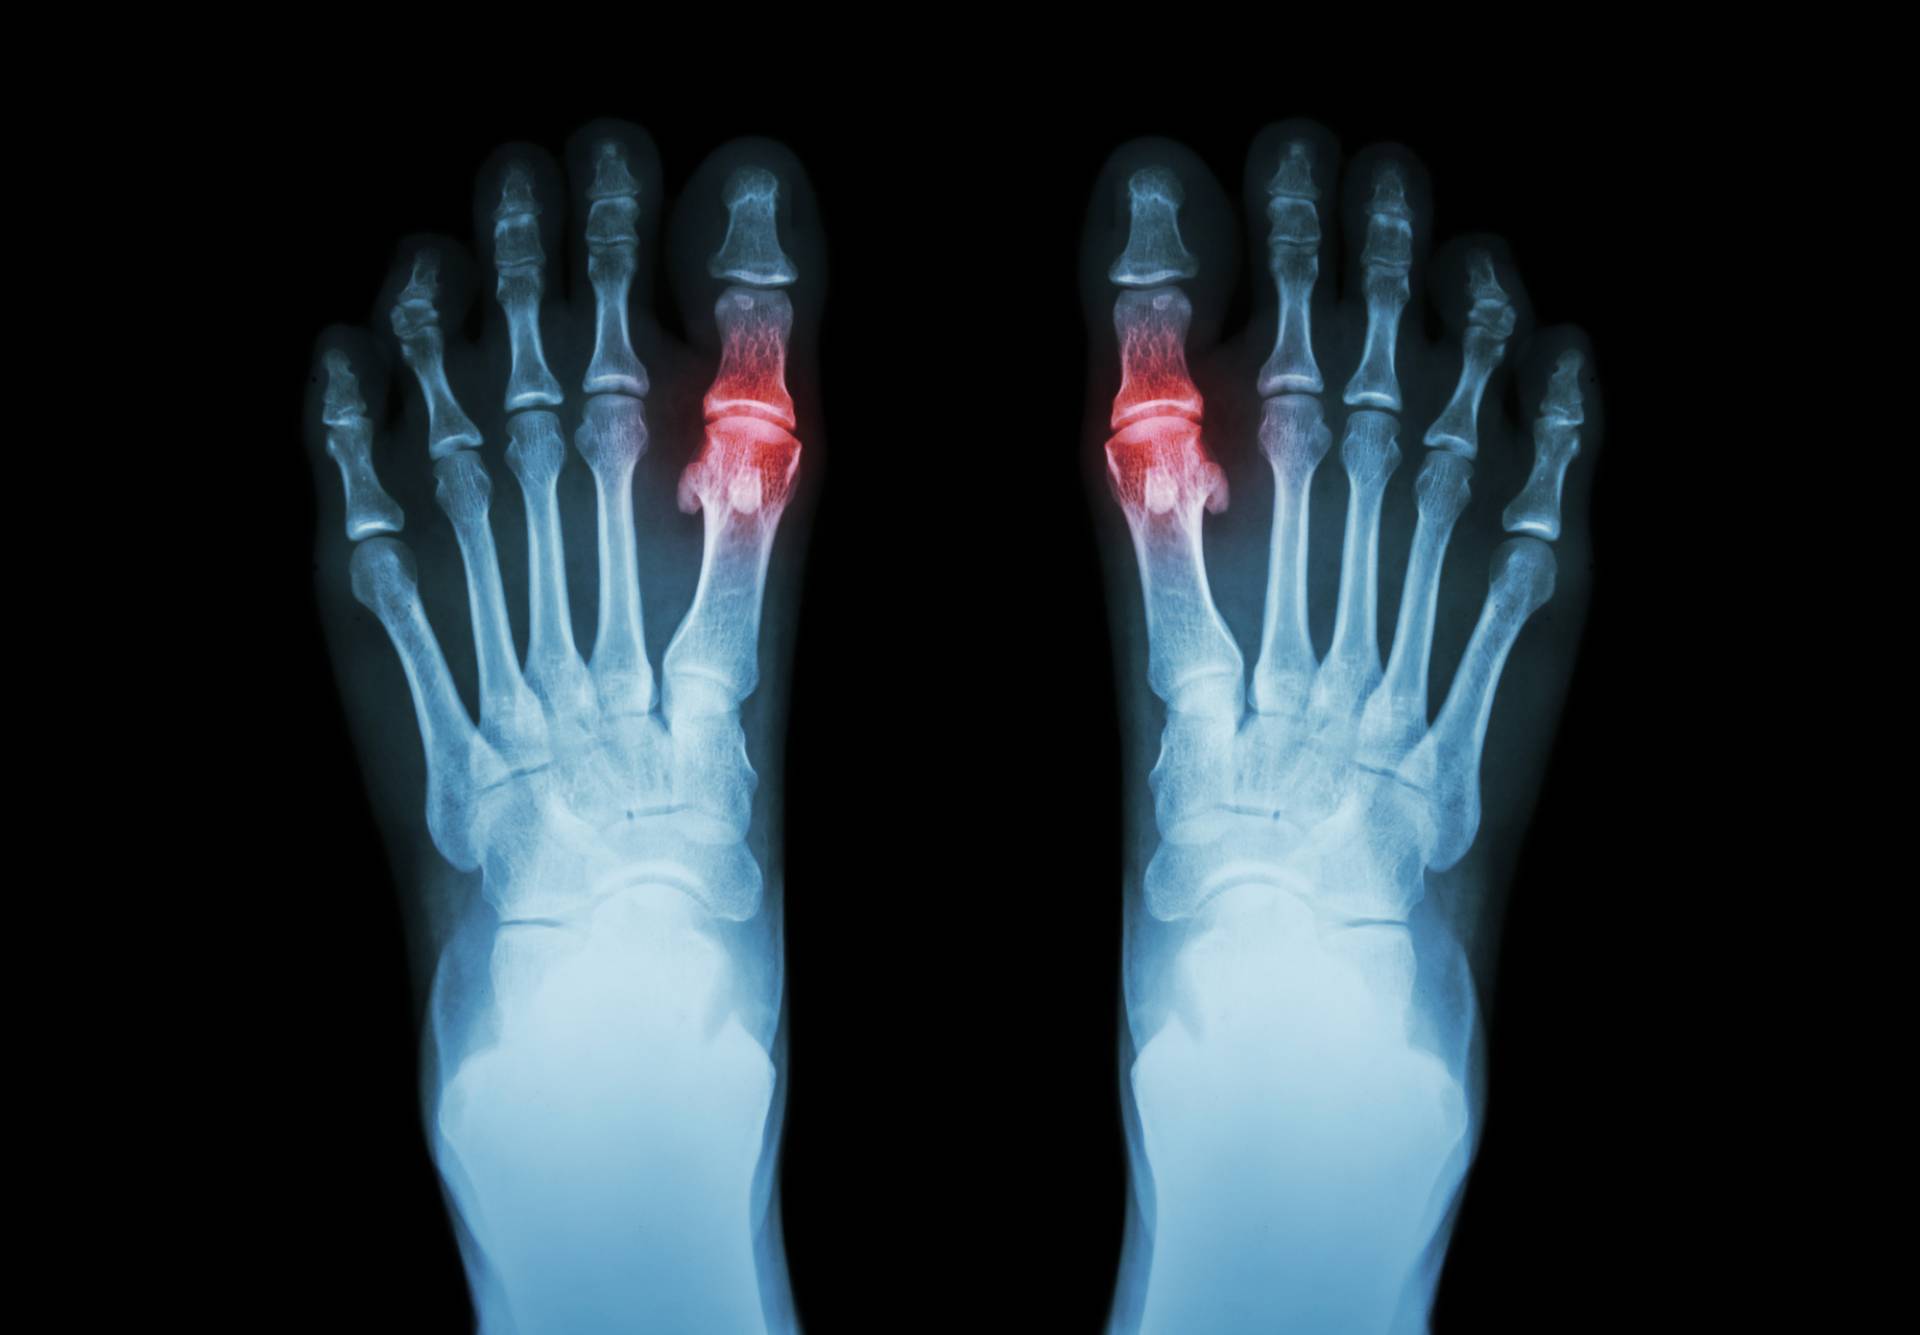

Sama choroba to choroba przewlekła, u której przyczyn leżą przede wszystkim zaburzenia przemiany materii. Najważniejsze jej objawy to zniekształcenia w obrębie stawów, zarówno kończyn górnych, jak i dolnych. Początkowo choroba tylko uprzykrza życie, powoduje ból, trudności z poruszaniem się, natomiast w zaawansowanym stadium nieodwracalnie uszkadza narządy ruchu. W skrajnych przypadkach poruszanie się jest zupełnie niemożliwe, a do tego dochodzą takie problemy jak guzki w tkankach i uszkodzenia nerek.

W przypadku dny moczanowej bardzo ważna jest szybka reakcja na pierwsze objawy. Niestety objawy czasami nie są proste do zaobserwowania. Przez dłuższy czas choroba nie daje żadnych objawów, co też jest znaczące i rozwija się po cichu. Dopiero z czasem zaczynają się bóle stawów, zazwyczaj ból w stopie, w obrębie palucha lub ścięgna Achillesa i ból pięty. Jest to bardzo zwodnicze, gdyż w obrębie pięty czuć ból także w przypadku ostrogi piętowej. Poza paluchem bóle odczuwalne są także w kolanach, nadgarstku, stawie barkowym oraz w obrębie całego kręgosłupa. Wraz z rozwojem choroby odczuwanie bólu i dyskomfortu ze strony mięśni zaczyna narastać. Pojawia się rano lub wieczorem, z czasem codziennie, pojawia się sztywność stawów i trudność w manewrowaniu kończynami. Stopniowo poza bólem pojawia się obrzęk, tkliwość podczas dotykania, zaczerwienienia skóry stawów oraz jej napięcie.

Choć istnieją schorzenia o podobnych objawach dnę moczanową można zdiagnozować bardzo szybko. Wystarczy zbadać poziom kwasu moczanowego w surowicy krwi, aby mieć pewność, że to nie ostroga piętowa ani inny rodzaj zapalenia stawów, lecz właśnie podagra. Jeżeli po badaniu wyniki wskażą, że stężenie kwasu jest wysokie, świadczy to o rozwoju choroby. Wynika to z faktu, że kryształki moczanu odkładają się w stawach działając destrukcyjnie na ich tkankę i powodując wszystkie związane z chorobą dolegliwości. Skierowanie na badania powinien zlecić lekarz, zwłaszcza jeśli wcześniej leczył bóle stawów i nic nie pomagało, brak poprawy to wskazówka, że leczy się nie ten problem, który trzeba.